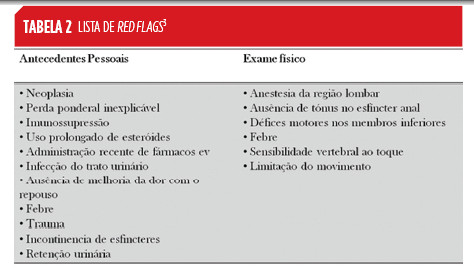

Devida à extensa lista de diagnósticos diferenciais, foram criadas red flags (Tabela 2), cuja presença durante a história clínica e/ou exame objetivo, implica um estudo etiológico mais aprofundado.